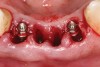

Figure 1  Preoperative clinical condition.

Figure 1

A 53-year-old male presented with localized advanced periodontal disease of the mandibular incisors. Teeth Nos. 23 to 26 exhibited Class II mobility because of advanced bone loss (Figure 1). The teeth had migrated out of position over the years, and a diastema had developed between No. 24 and No. 25 (Figure 2). The patient complained about the poor esthetic appearance of these teeth, and he was able to perceive their loss of strength on function as a result of their mobility.